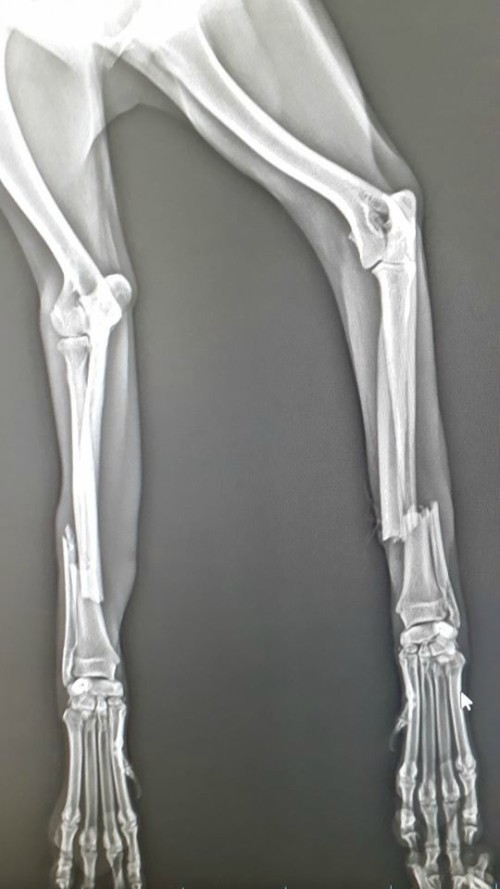

Otomobilin çarpması sonucu 2 ayağı kırılan köpek, İnegöl Belediyesi Sahipsiz Hayvanlar Bakım ve Tedavi Merkezi’nde yapılan operasyon ile sağlığına kavuşturuldu.

İnegöl Belediyesi Sahipsiz Hayvanlar Bakim ve Tedavi Merkezi’nden yapılan açıklamaya göre, otomobilin çarpması sonucu iki ayağı kırılan köpek, Sahipsiz Hayvanlar Bakim ve Tedavi Merkezi ekiplerince tedavisi yapılmak üzere merkeze getirildi.

Merkezde tedavisi gerçekleştirilen köpeğin kırıkları tespit edilirken, ameliyat gerekliliği nedeni ile bıçak altın yatırıldı. Yapılan başarılı operasyonun ardından iki ayağı kırılan köpek sağlığına kavuşturuldu.